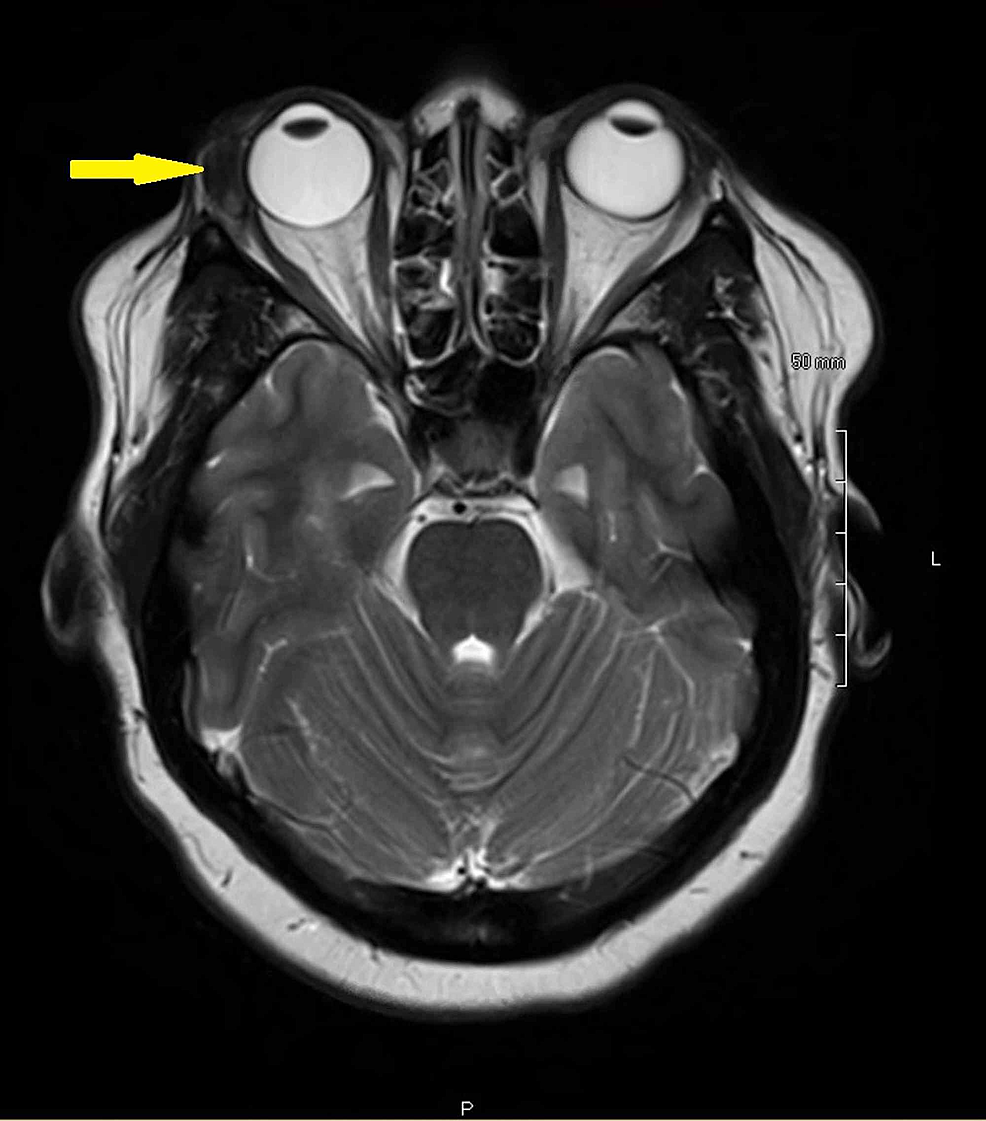

Radiology Anatomy Images Orbit MRI Anatomy Ct Anatomy Of Lacrimal Gland Learn about the lacrimal gland, an exocrine gland that secretes lacrimal fluid (tear fluid) onto the eye surface. Ct is often the initial modality of choice because it delineates the lacrimal system anatomy, shows most nasolacrimal drainage apparatus abnormalities and their extent, and facilitates preoperative planning. The lacrimal gland produces the watery part of tears that lubricate and protect the. Ct Anatomy Of Lacrimal Gland.